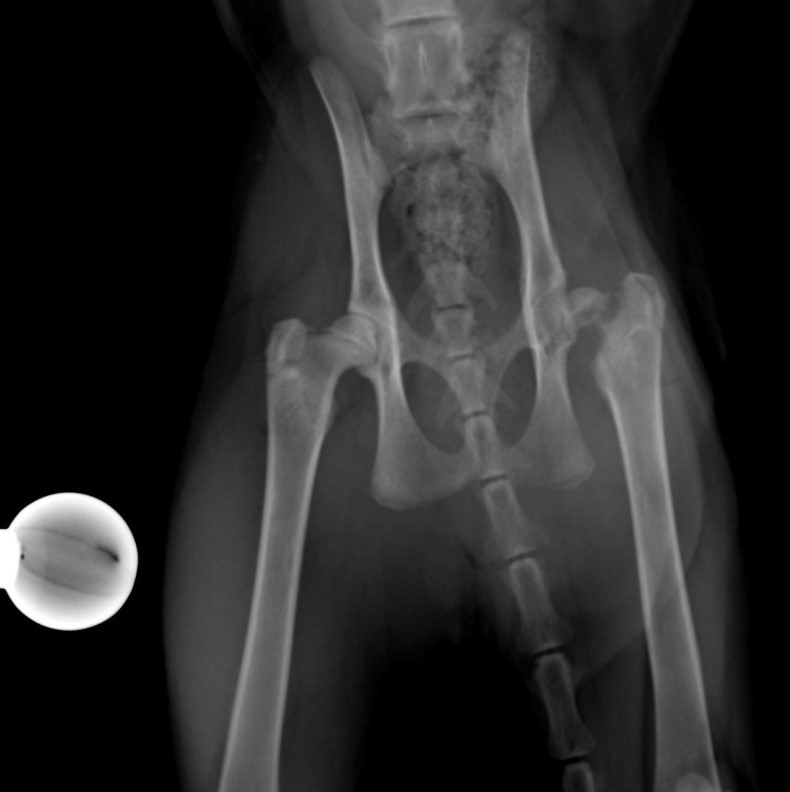

Nekróza krčku stehenní kosti u kočky - FHO

Případy z praxe

Akutní

případ